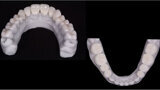

Fig. 12. Carillas y coronas finales preparadas digitalmente con el software de diseño Ceramill Mind y producidas en una fresadora (Ceramill Motion 2) a partir de bloques de cerámica de disilicato de litio mecanizables (VITABLOCS TriLuxe forte).